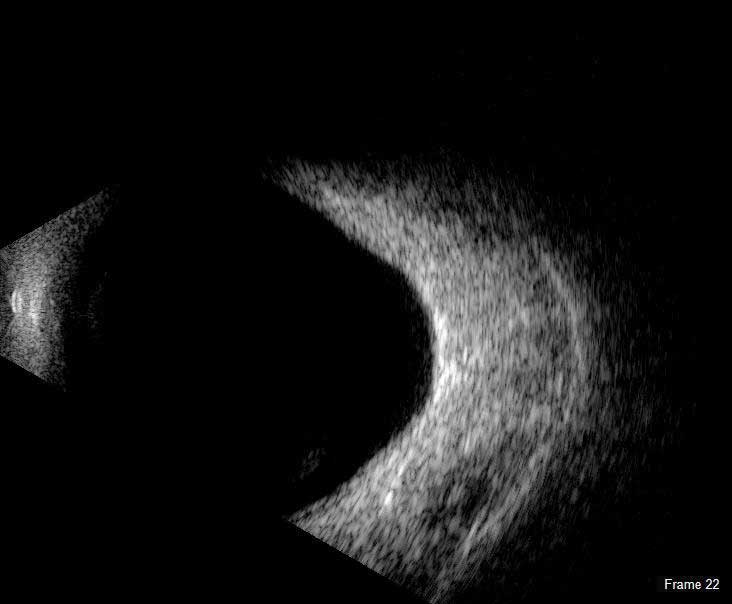

The DGH 8000 B-Scan combines the most advanced ultrasound technology available with the processing power, data storage and connectivity advantages of a personal computer. The DGH 8000 is equipped with dual 12.5 MHz and 15 MHz frequencies in the same probe, which results in a unique depth selection range from 3 cm and 6 cm in 12.5 MHz mode and 5 cm and 10 cm in 15 MHz mode.

The DGH 8000 B Scan delivers clear images for the posterior portion, even when optical clarity is compromised:

- Retinal Detachments

- Vitreous Detachments

- Vitreous Humor Pathologies

- Staphylomas

- Posterior Segment Pathologies

- Choroidal Pathologies

- Optic Nerve Pathologies

- Scleral Thickening